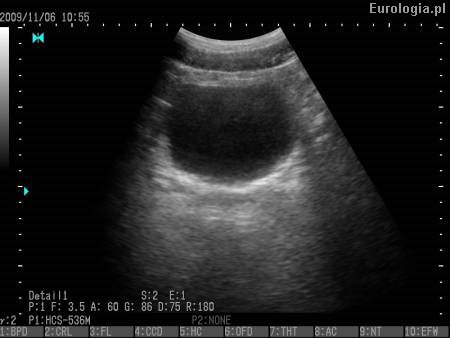

Prawidłowa pojemność pęcherza moczowego u osoby dorosłej wynosi 300 - 600 ml. Częstomocz nie musi mieć związku ze zmniejszeniem pojemności pęcherza moczowego. Konieczna jest ocena czy nie istnieje organiczna przyczyna opisywanych przez Pana dolegliwości. Warto wykonać badanie ogólne moczu i badanie USG jamy brzusznej z pełnym pęcherzem moczowym z oceną zalegania po mikcji.

Fot. Obraz USG pęcherza moczowego.